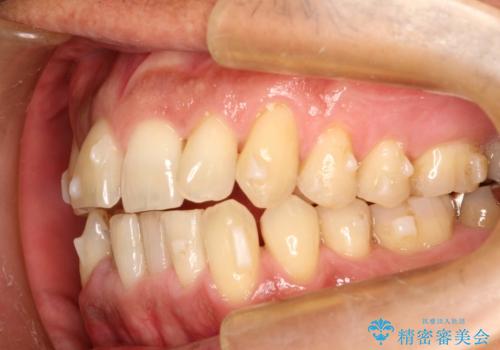

インビザライン invisalign ガタつきを治すマウスピース矯正

- 非抜歯・上顎臼歯遠心移動によるマウスピース矯正を計画した。

ガタつきを取り除くだけであれば非常に簡潔であるマウスピース矯正ですが、奥歯の位置関係の是正や、垂直的な歯の位置のコントロールなどが計画に含まれる場合、治療が難しくなってきます。